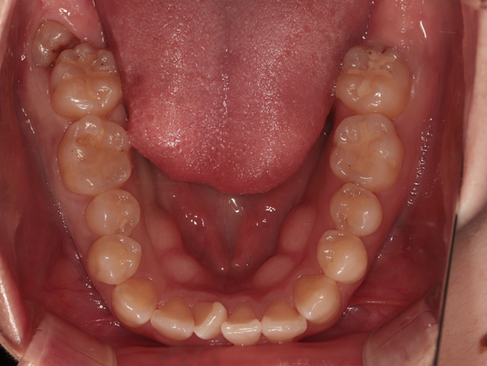

위 사진은 초진 시 아랫니 씹는면 구내사진입니다.

교정을 진행하지 않는 치아라면 위 정도의 초기우식은 정기검진하며 지켜볼 수는 있으나 교정장치를 붙이고 나면 안쪽에서 충치가 얼마나 진행되는지 등 정기검진을 하 수 없기에 레진으로 간단하게 치료를 하였습니다.

이상 충치로 인해 인레이 및 레진치료를 진행한 부산보철잘하는곳 환자의 치료사례였습니다.